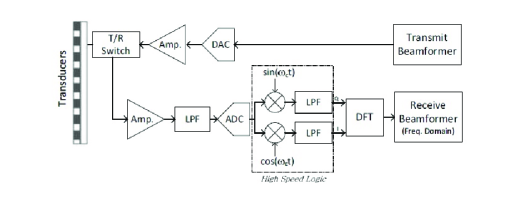

At this point of our work, as illustrated in Fig. 10, in-phase and quadrature components of the detected signals were used to obtain the desired set of their DFT coefficients.

Using this set, beamforming in frequency was performed according to (16) and (20), yielding the DFT coefficients of the beamformed signal. In this setup the sampling rate remained unchanged, but frequency domain beamforming was performed at a low rate. In our experiments we computed DFT coefficients of the beamformed signal, using DFT coefficients of each one of the detected signals. This corresponds to real-valued samples used for beamforming in frequency. The number of samples required by demodulated processing rate is . Hence, beamforming in frequency is performed at a rate corresponding to of the demodulated processing rate. Images obtained by low-rate beamforming in frequency and standard time-domain beamforming are presented in Fig. 11. As can be readily seen, we are able to retain sufficient image quality despite the significant reduction in processing rate.

Our implementation was done on a state-of-the-art system, sampling each channel at a high rate. Data and processing rate reduction took place following DFT, in the frequency domain. However, by implementing the Xampling scheme described in Section IV-B, the set of DFT coefficients of the detected signals, required for frequency domain beamforming, can be obtained directly from only real-valued low rate samples.